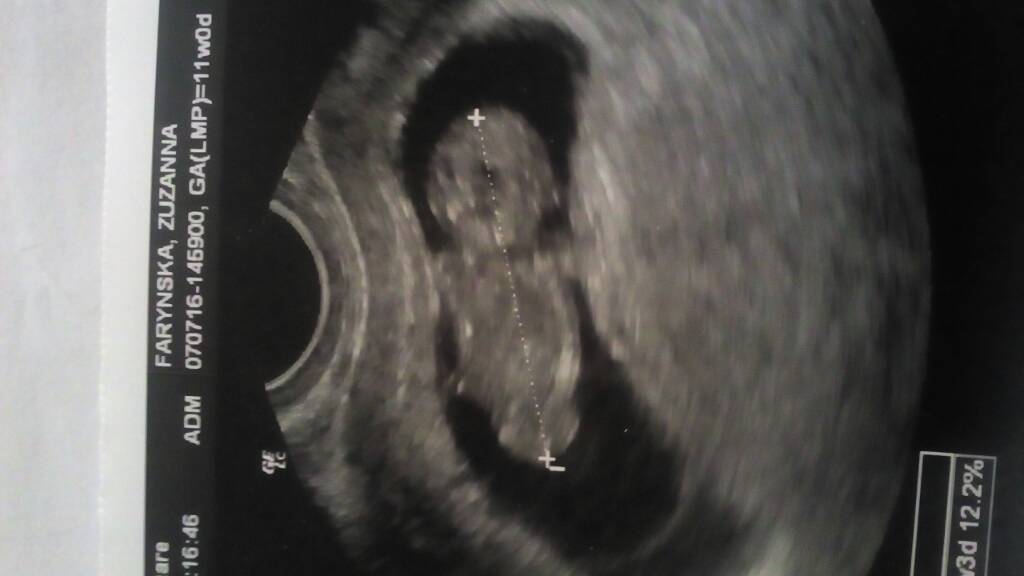

Dobra to teraz ja. Jestem pk wizycie. Wszystkie objawy ciąży minęły. Mdłości nie mam, cycki nie bolą. Szłam jak na ścięcie. W kolejce myślałam ze umre. A tu jest wszystko ok. Serduszko, tętno 162, wszystkie badania są rewelacja. Po ostatnich postach myślałam że bie doczekam do wizyty i obudzilam sie juz po 4. Zawał murowany. Na usg leżałam 40 minut bo sie maluch nie chciał odwrócić i tak dlugo go szturchał żeby jakas kość na twarzy zobaczyć. Maluch cały czas trzymał garde. Hehe